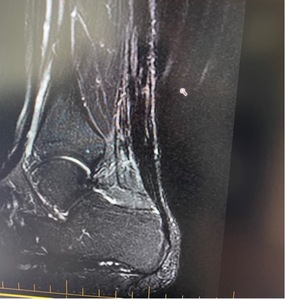

The patient elected to undergo surgery to treat this injury. The repair was augmented with the BioBrace implant due to the large gap and poor tissue quality in this tendon (Figure 2). BioBrace was used to assist in the healing process of this chronic tear and to fill the tendon defect by aiding in the re-growth of native tendon tissue (McMillan, Arciero, and Ford 2021). If BioBrace had not been available, the procedure would have been completed using an autograft, allograft, or the fascia flap turndown technique.